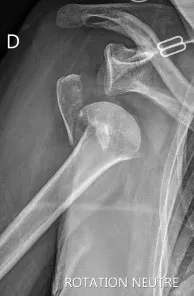

fracture neer 4

enclouage fracture 4 fragments épaule